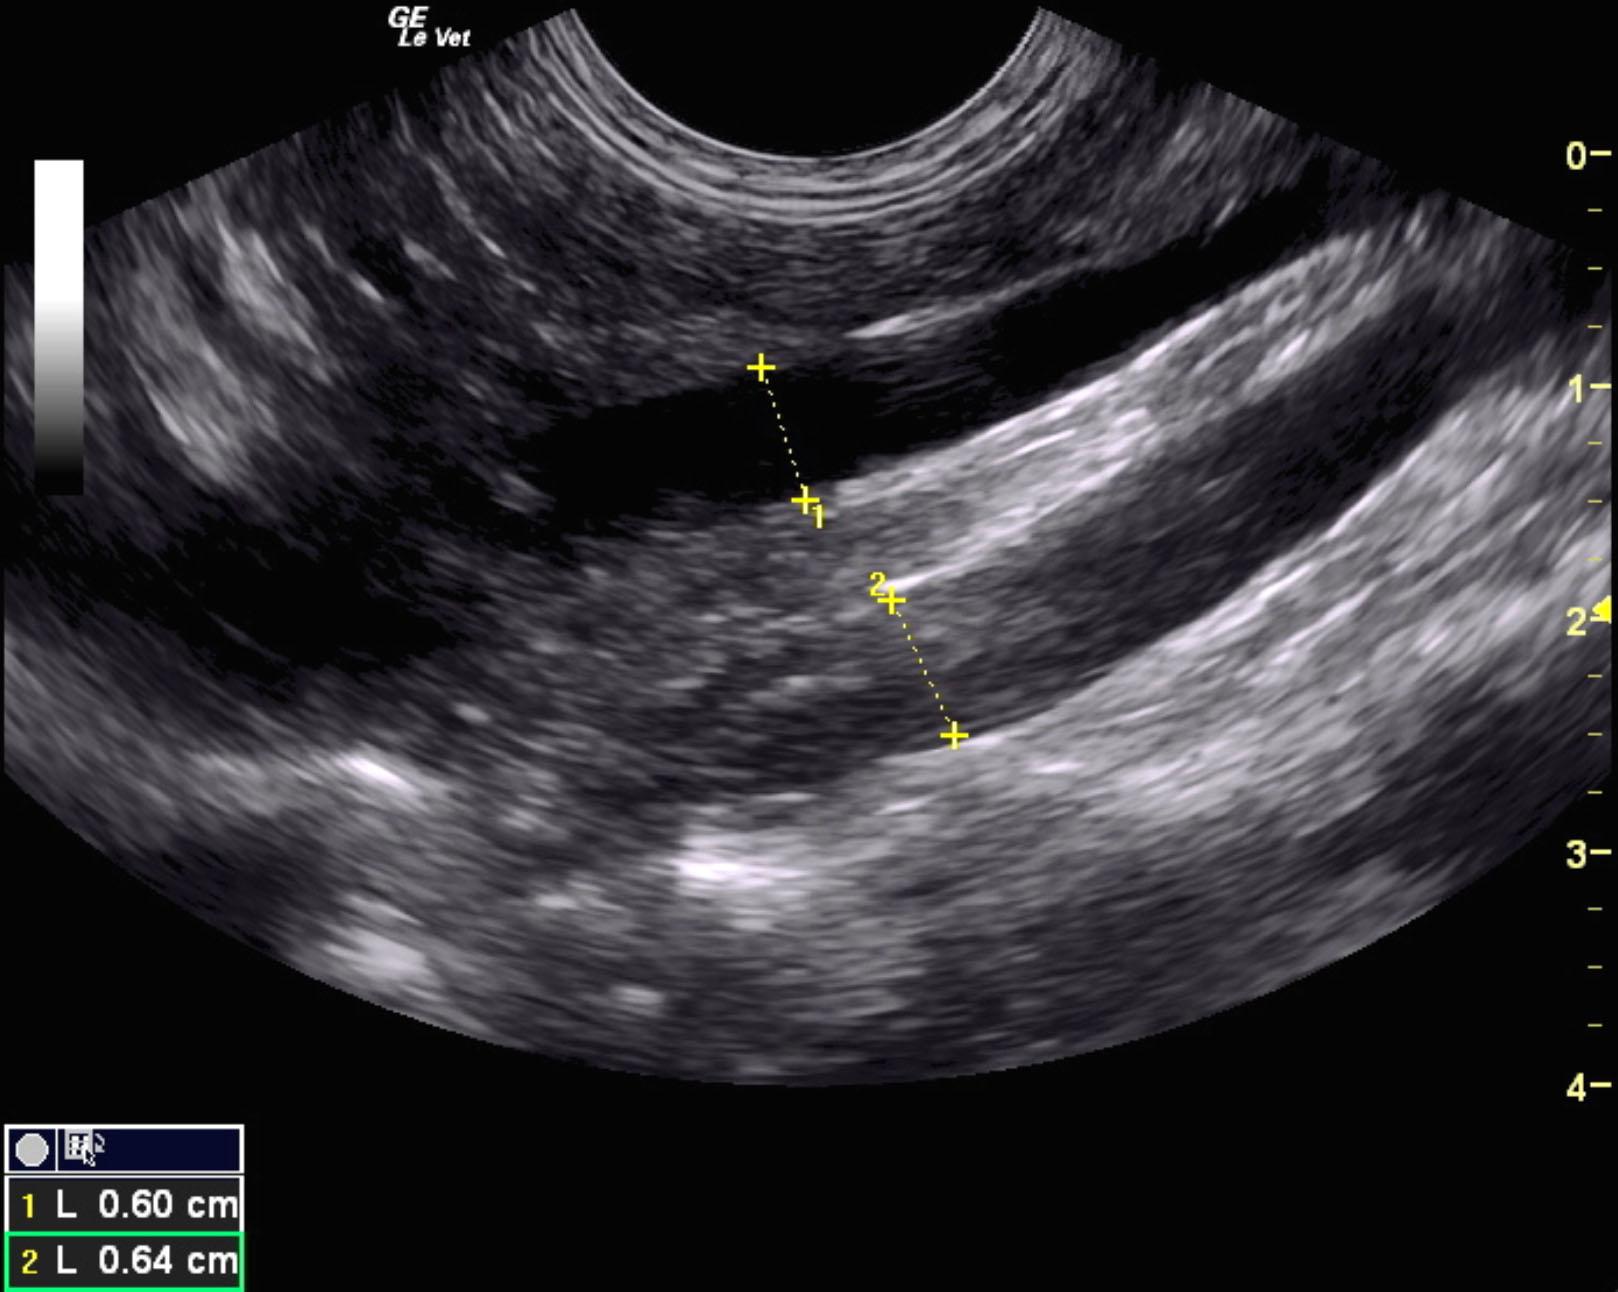

Extrahepatic portosystemic shunt was noted in this patient and measured 0.45 cm in width. The portal vein prior to the shunt measured 0.39 cm and post shunt measured 0.28 cm. This is most consistent with splenocaval shunt. The vena cava prior to the shunt entry measured 0.6 cm and the aorta measured 0.64 cm. The extrahepatic shunt passed dorsally and measured from 0.6 to 1.0 cm in width and entered into the vena cava dorsal ventrally prior to the diaphragm. The vena cava measured 1.0 cm at that point. The liver was subnormal in size and mildly coarse in architecture. The gallbladder was unremarkable.